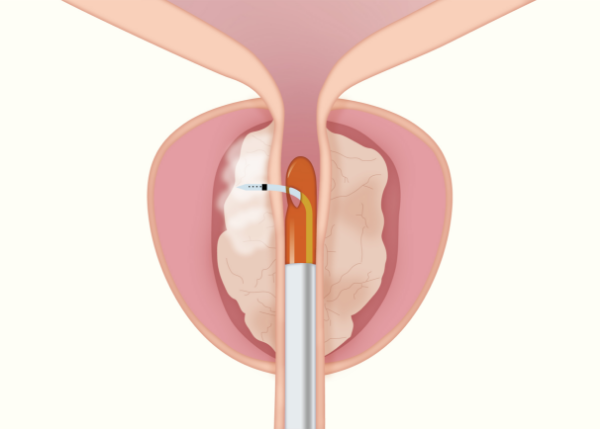

Rezumシステムは、内視鏡を用いて尿道から入り、水蒸気を利用して前立腺肥大症を治療する医療機器です。

肥大した前立腺組織内に103℃の水蒸気を9秒間噴霧し、組織を約70℃まで上昇させることで組織を壊死させます。

従来の前立腺肥大症に対する温熱療法と比べて、水蒸気を利用しているため対流によってムラのない治療効果が発揮され、尿道粘膜や性機能温存が可能です。